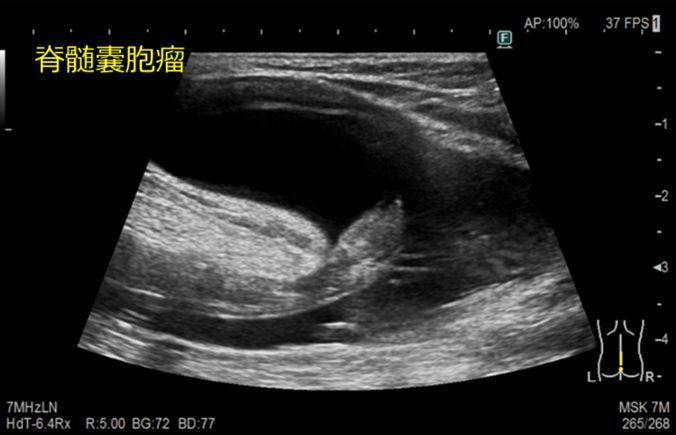

脊髄超音波検査

背中から超音波をあてて、脊髄病変の有無や性状の観察をします。

脊髄嚢胞瘤とは

髄液腔(拡大した脊髄中心管)が脊椎管外へ脱出する奇形のことです。

脂肪脊髄髄膜瘤とは

神経管閉鎖時に脊髄の背尾側に迷入発生する過誤腫性の奇形のことです。潜在性二分脊椎の原因の中で最も多い疾患です。